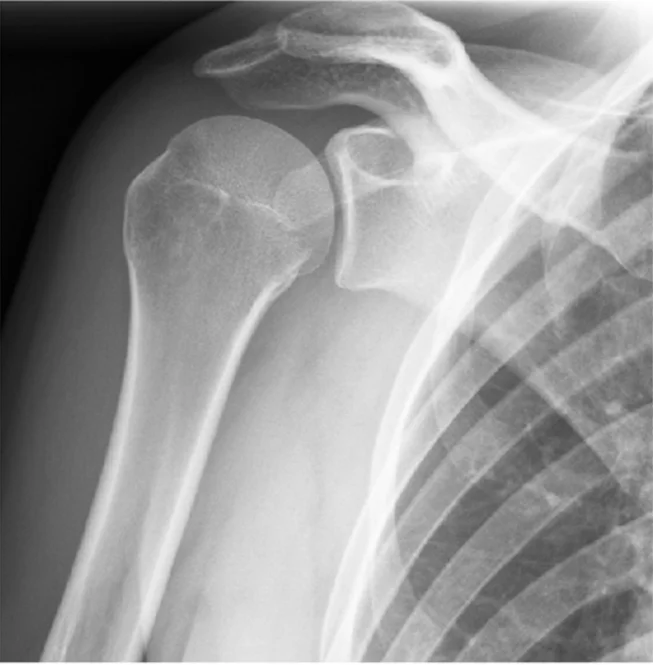

Patient: 17âyearâold male â fell from a bicycle, landing on his left shoulder.

Symptoms: Pain on shoulder movement; tender point medial to the shoulder; no skin lesions.

Imaging (Xâray, left side)

- Location: Middle third of the left clavicle

- Fracture type: Simple

- Fracture line: Transverse

- Displacement: Downward tilt of ââŻ35°

Special considerations: The fracture could be managed conservatively.

- Site: Greater tuberosity of the right humerus

- Type: Simple

- Fracture line: Vertical

- Displacements: None

- Special issues: Can be treated conservatively

Patient: 65âyearâold woman â slipped on a wet floor and fell onto her left shoulder.

Findings

- Site: upper humeral neck

- Type: comminuted fracture

- Fracture line: multiple (3âpart)

- Displacement: minimal

- Special issues: treated conservatively